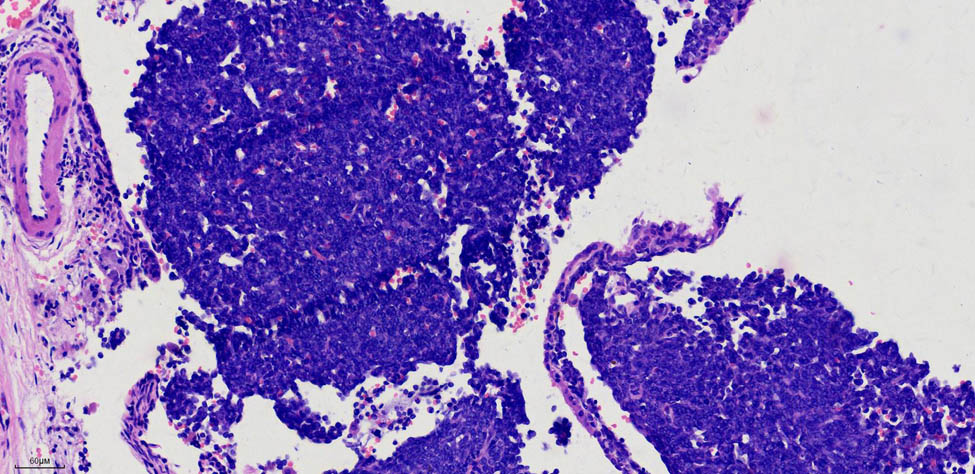

Pathological findings (202311954) indicated a 1.3 cm × 1 cm mass located in the dorsal bronchus of the right lower lobe, which appeared soft with a grey–red cut surface. Routine histological examination identified a spindle cell tumour in the right lower lobe, with immunohistochemistry suggesting a sarcoma, measuring 1.3 cm × 1 cm, with no pleural invasion. Lymph nodes from groups (2, 4), (7), (10), and (11), which represent the left cardia lymph nodes, the lymph nodes around the left gastric artery, the splenic hilum lymph nodes, and the lymph nodes around the splenic artery, respectively, exhibited no metastasis (0/5, 0/1, 0/2, and 0/1, respectively). The immunohistochemistry results were as follows: CK7 (−), TTF-1 (−), p40 (−), Syn (−), CgA (−), CD56 (+), INSM1 (−), Ki-67 (30%), D2-40 (−), CR (−), TTF-1 (−), CyclinD1 ( +), CK (−), EMA (−), p63 (−), FLI-1 ( +), CD117 (−), desmin (−), SATB2 (−), Vim (+), INI-1 (+), calponin (−), CD99 (−), NKX2.2 (minimal), Pan-Trk (−), WT1 (−), ER (−), SMA (−), and STAT6 (−) (Figure 4). Special staining for elastic fibres was negative. On 16 October 2023, a pathology consultation from Fudan University Shanghai Cancer Centre confirmed the diagnosis of SS in the right lower lobe. The immunohistochemical findings (HI23-34100) were S-100 (−), SOX10 (−), HMB45 (−), NKX2.2 (minimal+), SS18–SSX (+), AE1/AE3 (individual+), and SMARCA4 BRG1 (+, no missing).

Aggregation of short spindle-shaped cells under a microscope. H&E staining, 20× magnification image.

SS grows in four patterns: poorly differentiated monophasic, biphasic, monophasic fibrous (spindle cells), and monophasic epithelial. The monophasic pattern is characterised by spindle cells with minimal cytoplasm and hyperchromatic nuclei that are round, oval, or short spindle-shaped, often without clear divisions. SS typically displays various morphological features, such as interstitial mucinous degeneration, cystic degeneration, ossification, and hemangiopericytoma. The biphasic pattern features a mix of spindle and epithelial-like cells. Focal epithelial areas can be seen amidst the spindle cells, often exhibiting cleft-like, glandular tubular, or papillary structures, with round nuclei, granular chromatin, occasional nucleoli, and mild mucin secretion [6].

In this case, the tumour was primarily composed of short spindle cells, consistent with the monophasic fibrous pattern. Immunohistochemically, SS is generally positive for vimentin, CK, CK7, CK19, EMA, BCL-2, and CD99, whereas it is only positive for SMA and calretinin in some cases. More than 30% of SS cases exhibit nuclear and cytoplasmic positivity for S-100, whereas CD34 and desmin are typically negative [7]. This patient was negative for CK, CK7, EMA, SMA, and S-100, as assessed through immunohistochemistry, which complicated the diagnosis because of the unsatisfactory expression of certain markers.